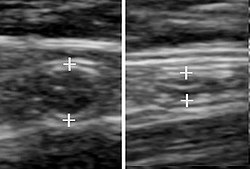

Abdominal ultrasonography, preferably with doppler sonography, is useful to detect appendicitis, especially in children. Ultrasound can show the free fluid collection in the right iliac fossa, along with a visible appendix with increased blood flow when using color Doppler, and noncompressibility of the appendix, as it is essentially walled-off abscess. Other secondary sonographic signs of acute appendicitis include the presence of echogenic mesenteric fat surrounding the appendix and the acoustic shadowing of an appendicolith.[45] In some cases (approximately 5%),[46] ultrasonography of the iliac fossa does not reveal any abnormalities despite the presence of appendicitis. This false-negative finding is especially true of early appendicitis before the appendix has become significantly distended. Also, false-negative findings are more common in adults where larger amounts of fat and bowel gas make visualizing the appendix technically difficult. Despite these limitations, sonographic imaging with experienced hands can often distinguish between appendicitis and other diseases with similar symptoms. Some of these conditions include inflammation of lymph nodes near the appendix or pain originating from other pelvic organs such as the ovaries or Fallopian tubes. Ultrasounds may be either done by the radiology department or by the emergency physician.[47]

Ultrasound showing appendicitis and an appendicolith[48]

Ultrasound of a normal appendix for comparison

A normal appendix without and with compression. Absence of compressibility indicates appendicitis.[45]